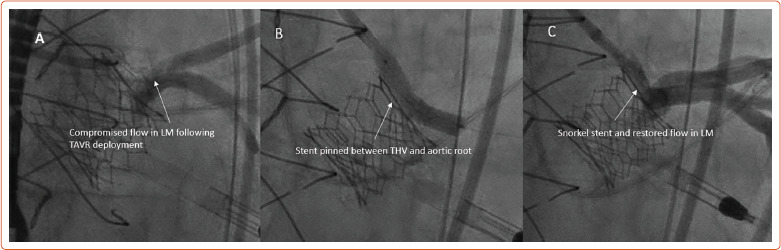

While redo surgical aortic valve replacement has traditionally been the gold standard for the treatment of failed surgical valves, valve-in-valve (ViV) transcatheter aortic valve replacement (TAVR) has arisen as a viable, less invasive option with the potential for improved short-term morbidity and mortality. Retrospective registry data regarding ViV TAVR outcomes have been encouraging, with excellent 1-year mortality, and sustained valve performance and quality of life improvement out to 3 years. Operators must be comfortable with CT analysis for procedural planning, and be able to identify and troubleshoot patients who are at risk for coronary obstruction and patient prosthesis mismatch. The authors provide a review of clinical outcomes associated with ViV TAVR, procedural planning recommendations, and strategies to overcome technical challenges that can occur during ViV TAVR.